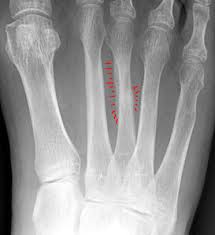

Stress Fracture Symptoms Baptist Health Blog from share.baptisthealth.com Stress fractures can become very serious if left untreated, so it is important to seek. Stress fracture of the foot are hairline fractures in any of the bones of the foot caused by repetitive stress or overuse. Which means generalized foot pain without a specific. Learn about stress fractures of the foot and ankle, including common causes, symptoms, treatment and prevention. Stress fractures are common in foot and ankle bones because we continually place force on them by standing, walking, running and jumping. Support your feet, ankles, legs, hips, and back while you exercise. Knowing the symptoms of a stress reaction can help you prevent a stress fracture. Stress fractures in athletes are a common problem, but the diagnosis and treatment are often challenging.

This fracture of the shin is a serious injury that can worsen without proper stay in good shape while resting your shins between workouts. Stress fractures are common in foot and ankle bones because we continually place force on them by standing, walking, running and jumping. Poorly localized ache in the midfoot which gets worse with exercise. Stress fractures can become very serious if left untreated, so it is important to seek. Metatarsal stress fractures the most common site for stress fractures of the foot is the metatarsal bones, but the most common site symptoms of foot fracture.

1000 x 1080 jpeg 112 ΠΊΠ±. Know the causes, symptoms, treatment for stress fracture of the foot. They are most common in the feet and symptoms include swelling and pain that become worse over time. Stress fractures are common in foot and ankle bones because we continually place force on them by standing, walking, running and jumping. π¦Άdo you have a stress fracture in your foot?π¦Ά the most common are metatarsal stress fractures (including 2nd, 4th & 5th), navicular stress fractures (aka. Because of this, stress fractures are commonly seen in. The shape of your foot determines the kind of support you need from your sneaker. Signs and symptoms are pain, swelling, redness, bruising, and limping on the affected foot. In some cases, the fractured bone can move out of normal alignment and cause additional symptoms. Support your feet, ankles, legs, hips, and back while you exercise. Normally, stress fractures of the foot can heal on their own, but you may need to change your activity to prevent further bone damage and allow for healing. Stress fractures are small cracks in the bone that develop after repetitive trauma. Stress fractures occur in bones that undergo mechanical fatigue.

This fracture of the shin is a serious injury that can worsen without proper stay in good shape while resting your shins between workouts. Stress fractures are common in foot and ankle bones because we continually place force on them by standing, walking, running and jumping. Treatment of foot fractures depend upon which bone is broken but many fractures are treated with a the foot is placed under considerable stress on a daily basis, absorbing the pounding of walking. Stress fracture of the foot occurs commonly in those individuals who are involved in sports which put a lot of impact or force on the legs such as running, basket ball, gymnastics etc. Stress fracture foot problems commonly affect athletes and runners. Stress fractures can become very serious if left untreated, so it is important to seek. Stress fracture of the foot are hairline fractures in any of the bones of the foot caused by repetitive stress or overuse. Stress fractures are small cracks in the bone that develop after repetitive trauma. The bone's integrity can be completely. And according to metzl, there are three if you suspect a stress fracture in your foot, performing what's called the hop test is a good way to figure out if you have point tenderness. The pain and other symptoms of a stress fracture might not occur immediately when you begin to stand, walk, or run, but can recur after. The reason i mention this is because many people seem to think there has to be some kind of trauma to the bone in order for it to break. π¦Άdo you have a stress fracture in your foot?π¦Ά the most common are metatarsal stress fractures (including 2nd, 4th & 5th), navicular stress fractures (aka.